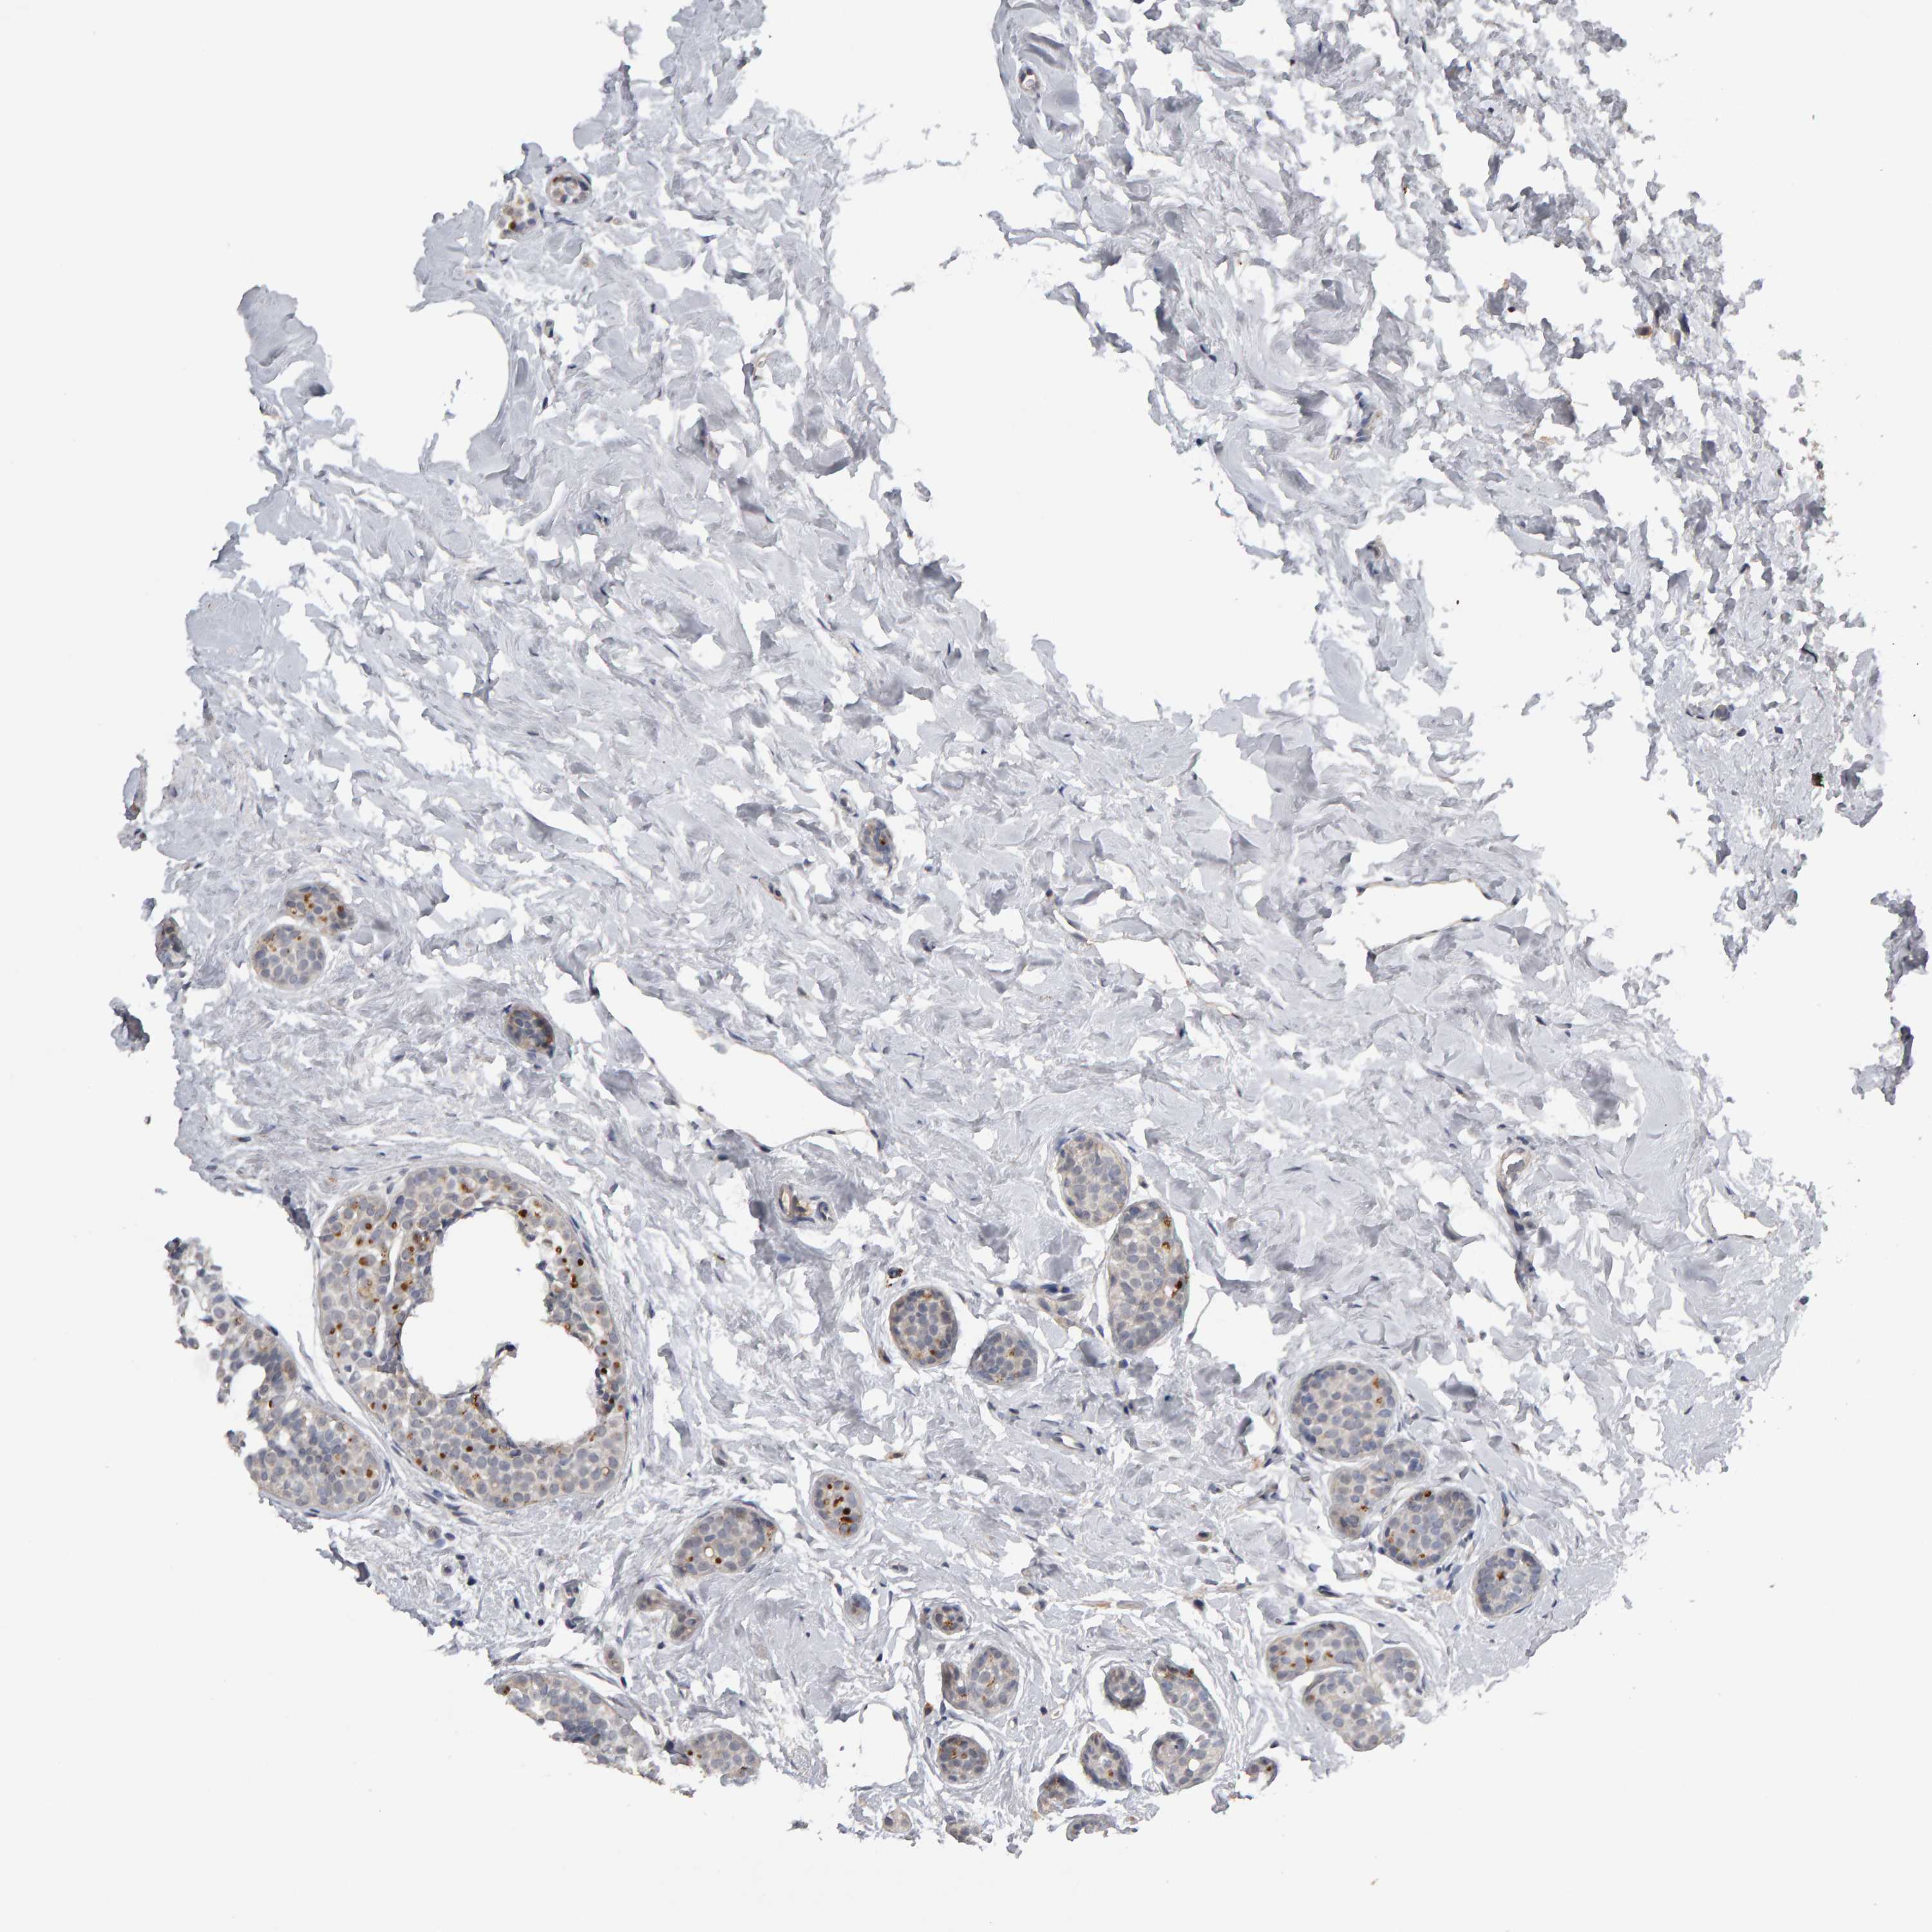

CANCER BREAST CANCER Show tissue menu

BRCA TCGA BRCA VALIDATION PROTEIN EXPRESSION